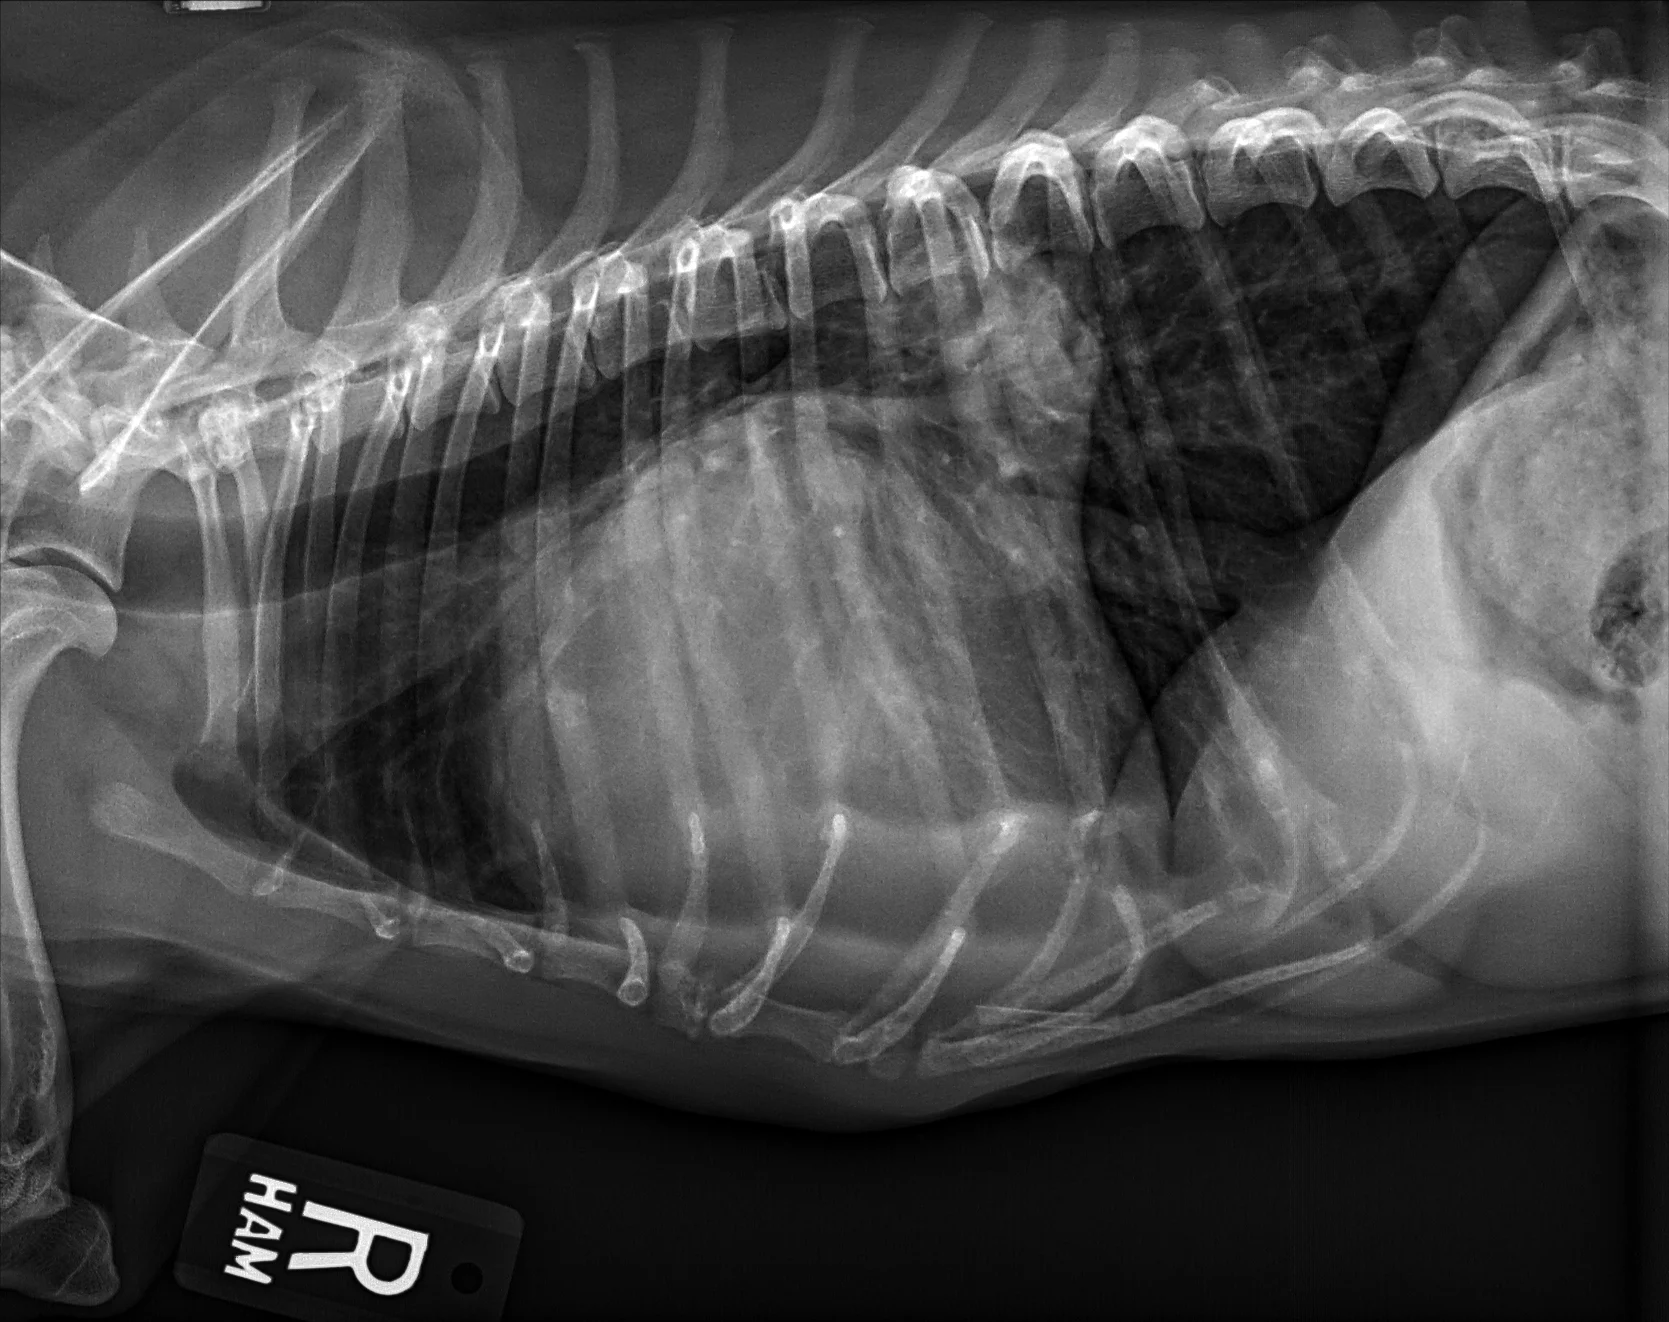

At least 2 orthogonal views, ideally taken during peak inspiration, are necessary for appropriate radiographic study of the cardiovascular system; however, a 3-view study is ideal for comprehensive evaluation of the thorax. Some differences should be considered when deciding to acquire a right versus left lateral projection and a dorsoventral (DV) versus ventrodorsal (VD) projection. On the left lateral view, the cardiac silhouette is typically more rounded and the apex is further elevated from the sternum than in the right lateral view (Figure 1). In the DV view, the cardiac silhouette is commonly displaced cranially and to the left by the diaphragm and appears more rounded than in the VD view. The caudal pulmonary vasculature is better delineated in the DV view, whereas the lung field (particularly the accessory lobe) is better evaluated in the VD view (Figure 2).

FIGURE 2 Normal DV (left) and VD (right) projections of the thorax in a large, crossbreed dog. The cardiac silhouette appears more rounded, and the caudal pulmonary vasculature is more apparent (arrowheads) in the DV view compared with the VD view. In some DV projections, the cardiac silhouette can appear significantly displaced to the left (not apparent in this case). Images courtesy of Federico Villaplana Grosso, DACVR, DECVR